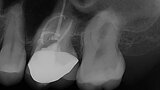

EdgeFile X7: Beastly bifurcation